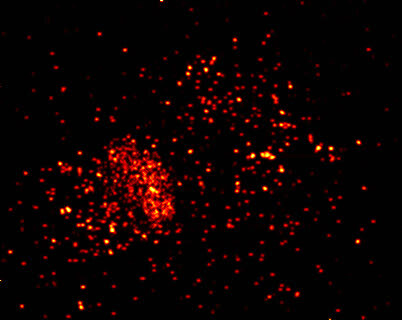

12.神经细胞与钙离子的精彩邂逅

钙离子一直都是神经细胞最重要的“信号离子”,通过显微注射技术将钙离子探针放进神经细胞中,使得探针和钙离子相互作用而产生荧光,钙信号在神经细胞中会像水波一样迅速向外扩散。